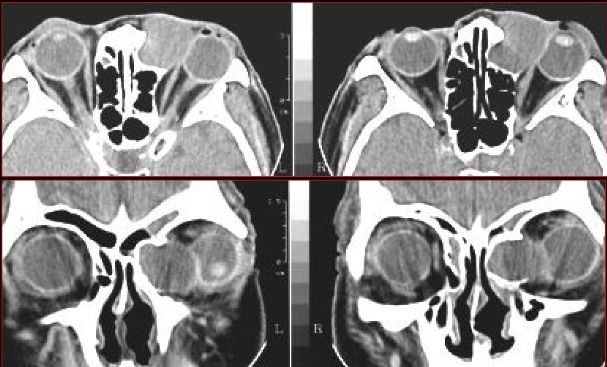

急性鼻窦炎

筛窦异物伴急性感染